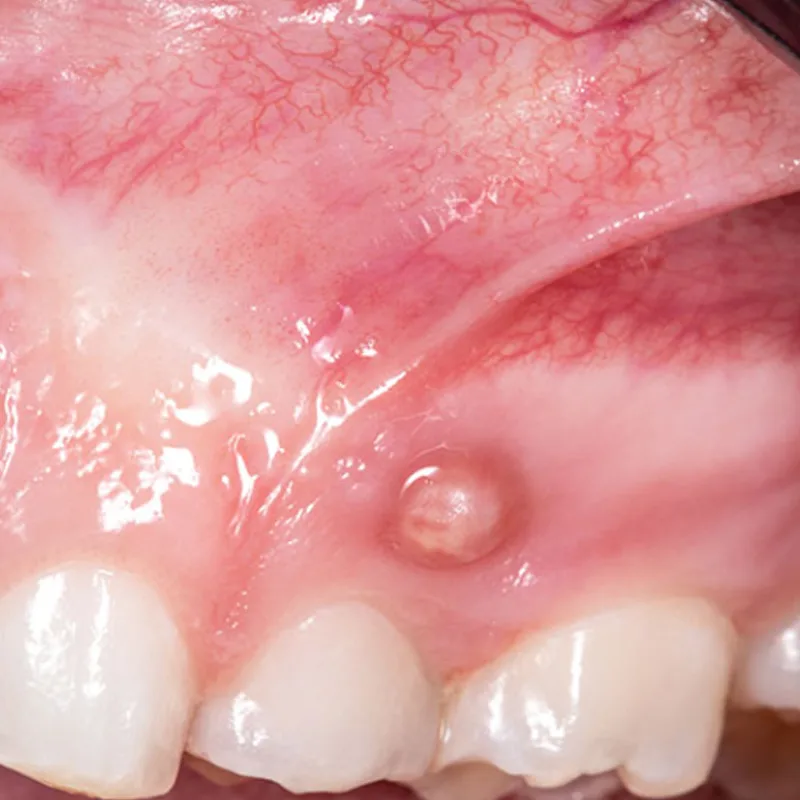

Fístula, bulto

Fístulas

Las fístulas son aberturas anormales que se forman en el tejido de las encías y pueden estar asociadas a infecciones o abscesos dentales. Suelen ir acompañadas de síntomas como dolor, inflamación o presencia de pus.

• Las fístulas se caracterizan por ser aberturas anormales en el tejido de las encías, a menudo conectadas a infecciones dentales.

• En el caso de fístulas en las encías, el tratamiento se centra en abordar la causa subyacente, como las infecciones dentales. Esto puede implicar drenaje del absceso, tratamiento antibiótico y posiblemente procedimientos dentales para corregir la fuente de la infección. Es importante buscar atención dental de manera inmediata para evitar complicaciones.